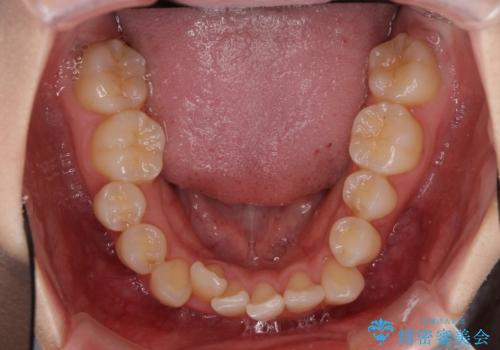

- 八重歯と奥歯の咬み合わせを気にして来院された患者様です。

インビザラインによる矯正治療を希望されたため、八重歯改善のための抜歯矯正部分は補助装置を併用し、その後はインビザラインにて行うこととしました。

下顎の右側変位が顕著であったため、ワイヤー矯正の方が咬み合わせは改善しやすいのですが、ある程度は時間がかかっても良いとのことであったので、インビザラインにて矯正治療を行うこととしました。